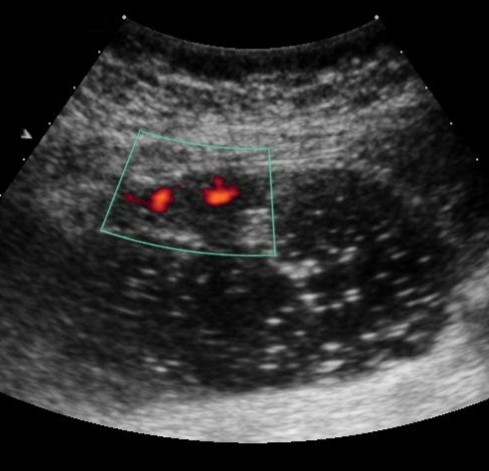

Weak vascularization was manifested in the form of a single point color vascular signals, the moderate vascularization - in the form of linear color vascular signals and the enhanced vascularization - in the form of wide color areas inside the tumor (Figure 16, Figure 17).

Figure 16.Distal gastric carcinomas of diffuse infiltrative form of T4 stage. Despite the large size of the tumor the vascularization is manifested in the form of single point color vascular signals.